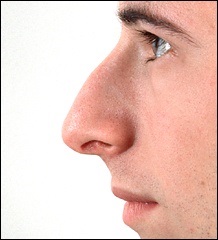

A fenti képek acanthion nagyon kis méretű. Valószínűleg ez része a csont megtört sok éve létezik a koponya. Ez a fejezet fog beszélni, amikor az orr gerinc nagyobb a szükségesnél.

Nézzünk egy másik három beteg, akiknek acanthion jelentősen rontja vonzerejét az orr.

A nő látható a felső fotó túl kiálló orrát. Ezt segíti elő a túlzott acanthion. Ezen kívül volt egy jelentősen nőtt a felső ajak. Amint azt a jogot, fotó, rövidítést követően az orrhegy és változtatni az alakját a felső ajak volt a hatása lerövidíti az orrát. Meg kell jegyezni, hogy ebben az esetben a hosszúkás gerinc nem vezet túlzott nyitó columella.

Itt is nincs túlzott nyitás columella, de van egy kiálló orr túl sok függőleges méretét.